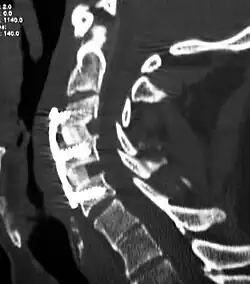

![]() X-rays of anterior cervical discectomy and fusion, C5C6 and C6C7. Lateral view. | |

To prevent the vertebrae from collapsing and to increase stability, the open space is often filled with a graft. That can be a bone graft, taken from the pelvis or cadaveric bone; or an artificial implant.[4] The slow process of the bone graft joining the vertebrae together is called "fusion". Sometimes a titanium plate is screwed on the vertebrae or screws are used between the vertebrae to increase stability during fusion, especially when there is more than one disc involved.